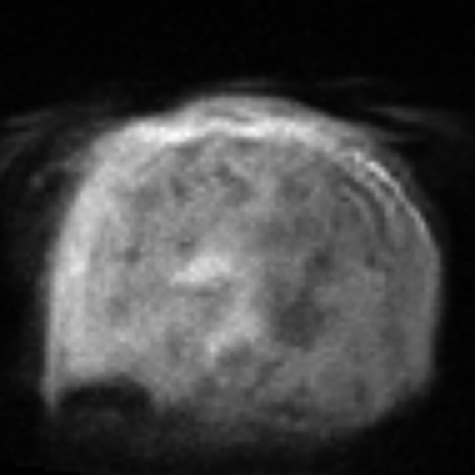

Assessing the severity of artifacts in pediatric brain Magnetic Resonance Imaging (MRI) is critical for diagnostic accuracy, especially in low-field systems where the signal-to-noise ratio is reduced. Manual quality assessment is time-consuming and subjective, motivating the need for robust automated solutions. In this work, we propose BRIQA (Balanced Reweighting in Image Quality Assessment), which addresses class imbalance in artifact severity levels. BRIQA uses gradient-based loss reweighting to dynamically adjust per-class contributions and employs a rotating batching scheme to ensure consistent exposure to underrepresented classes. Through experiments, no single architecture performs best across all artifact types, emphasizing the importance of architectural diversity. The rotating batching configuration improves performance across metrics by promoting balanced learning when combined with cross-entropy loss. BRIQA improves average macro F1 score from 0.659 to 0.706, with notable gains in Noise (0.430), Zipper (0.098), Positioning (0.097), Contrast (0.217), Motion (0.022), and Banding (0.012) artifact severity classification. The code is available at https://github.com/BioMedIA-MBZUAI/BRIQA.